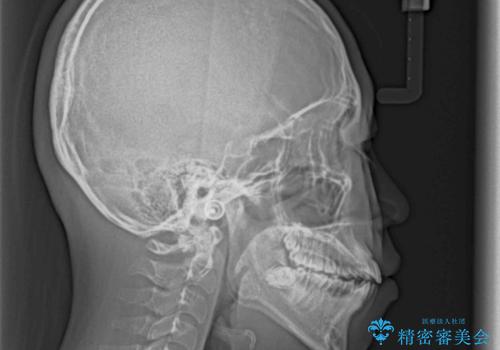

- 上下前歯の隙間と口元の出っ張った感じを気にして来院された患者様です。

上下の隙間は舌突出癖によるもので、またその癖により前歯が前方に出ている状態でした。

口元の出っ張りを改善するため、上下左右第一小臼歯4本を抜去し、ワイヤー装置にて矯正治療を行うこととしました。